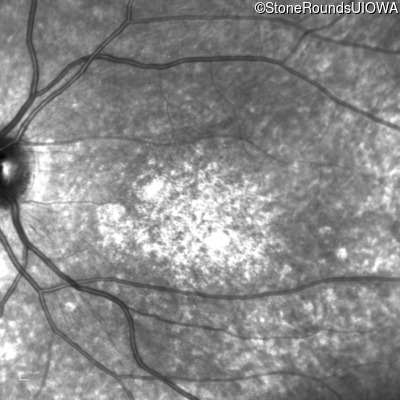

Age at visit: 15 years

OD OS

Age at visit: 16 years

Age at visit: 19 years

Age at visit: 23 years